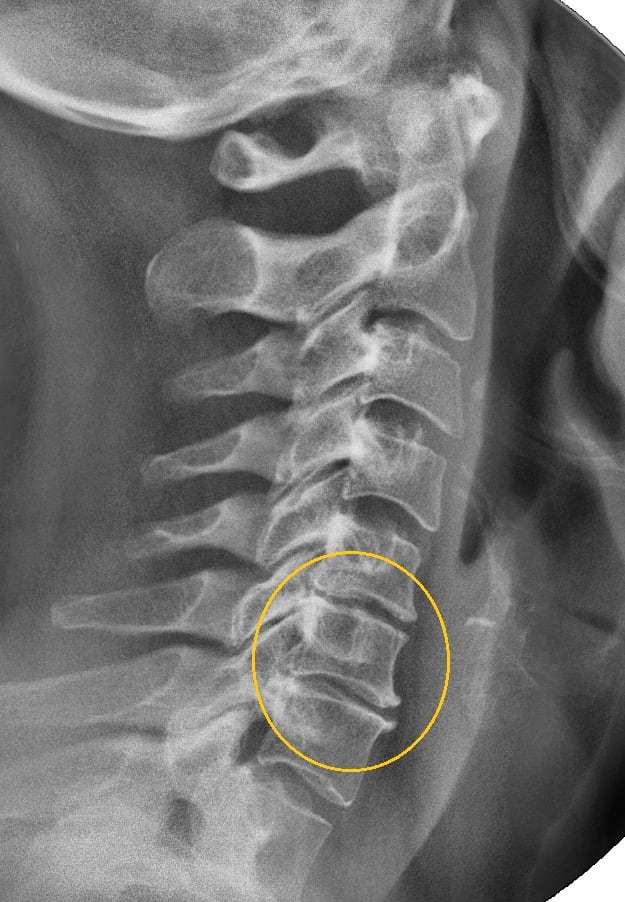

Связь между остеохондрозом и головным мозгом

Шейный остеохондроз оказывает негативное влияние на сосуды головного мозга. При заболевании позвоночника происходят патологические изменения в межпозвоночных дисках.

Недостаток питания приводит к их дистрофии, уменьшению расстояния между телами позвонков, трению. В ответ на механическое раздражение по костным краям образуются наросты (остеофиты), которые сдавливают артерии и нервные ткани.

Сосудистые нарушения провоцируют плохое кровообращение и недостаточную доставку кислорода к головному мозгу, вызывая ишемию.

Расстояние между позвонками сокращается, что приводит к их смещению, выпячиванию. В организме запускаются процессы стабилизациию структур шейного отдела. Края костных пластинок патологически разрастаются, формируя остеофиты.

Костные наросты сдавливают кровеносные сосуды, препятствуя кровоснабжению головного мозга. У пациента с остеохондрозом 2, 3 степени вертебрологи выявляют следующие неврологические расстройства: